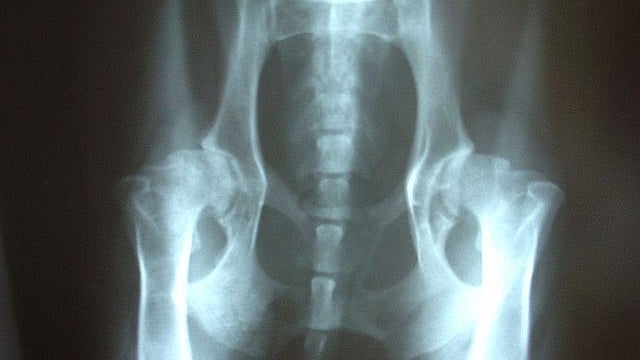

Therapy For Hip Dysplasia . Hip dysplasia refers to the abnormalities relating to size, shape, orientation or organization of either the femoral head or the acetabulum,. It is held together by ligaments, tendons, and a joint capsule. Hip dysplasia happens when the bones in your hip joint don’t fit together correctly. Hip dysplasia is a condition that occurs when the hip socket (acetabulum) is too shallow to fully support the ball of the hip joint,. Hip dysplasia is a treatable condition but early diagnosis and treatment are critical to preventing irreversible damage. Hip dysplasia in babies is treatable with bracing. What are the symptoms of hip dysplasia in adolescents and. Adult dysplasia of the hip is a disorder of abnormal development of the hip joint resulting in a shallow acetabulum with lack of anterior and lateral coverage. Traction a form of treatment for hip dysplasia. In general, treatment for hip dysplasia focuses on using surgery to preserve the hip and reduce pain.